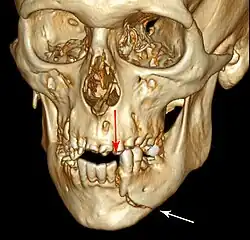

| 3D computed tomographic image of a mandible fracture in two places. One is a displaced right angle fracture and the other is a left parasymphyseal fracture. | |

Mandibular fracture, also known as fracture of the jaw, is a break through the mandibular bone. In about 60% of cases the break occurs in two places.[1] It may result in a decreased ability to fully open the mouth.[1] Often the teeth will not feel properly aligned or there may be bleeding of the gums.[1] Mandibular fractures occur most commonly among males in their 30s.[1]